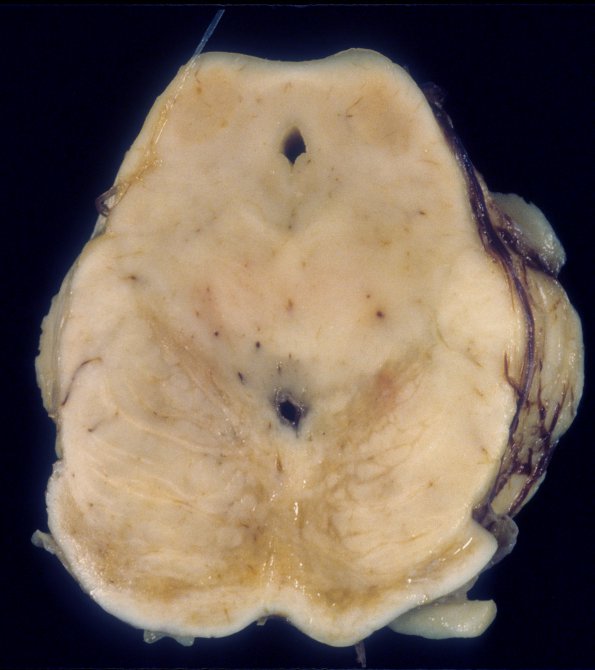

Washington University Experience | INFECTION | Viruses | PML (JC Virus) | PML - Gross Pathology | 2A1 PML (Case 2) A2

2A1,2 This case was characterized by extensive and unusual involvement of the brainstem, particularly sparing the descending corticospinal tracts in the brainstem (arrows, 2A2).